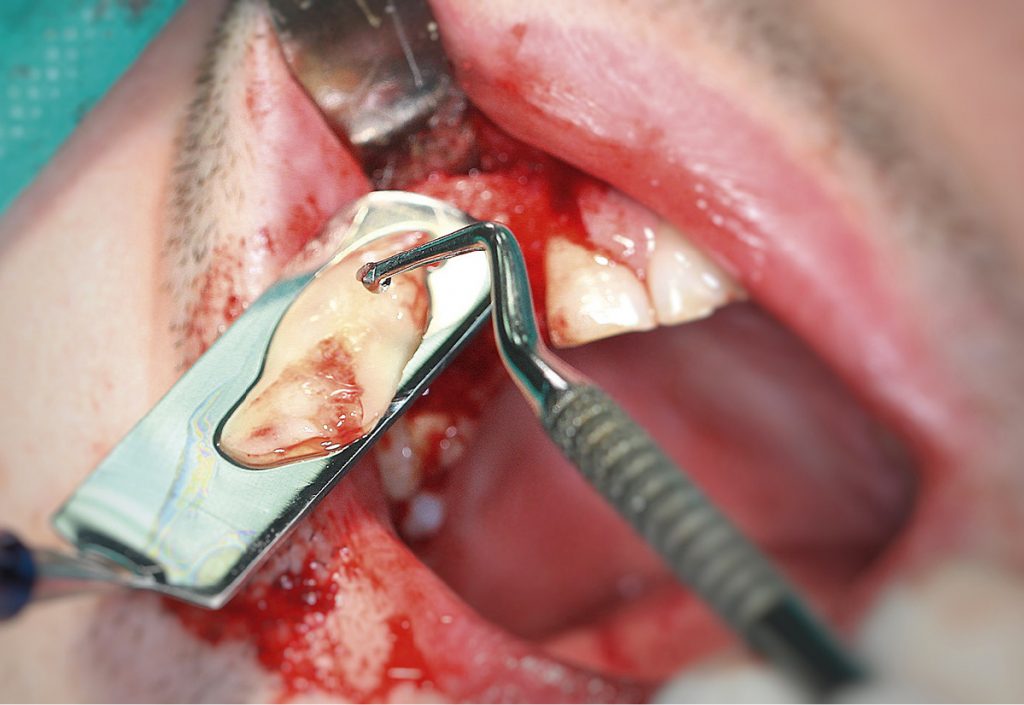

Summary: Oral surgeries aimed at the regeneration of alveolar bone can be performed using the autogenous dentinal matrix obtained from a patient’s own tooth. The obtained material is subjected to strictly defined procedures to reduce the amount of bacteria in the received augmentation material. The article presents a case in which the autogenic bone substitute material was obtained by grinding an impacted wisdom tooth which was used to augment the alveolar process in the maxilla after the extraction of teeth 12 and 13.

Wykonywane zabiegi z zakresu chirurgii stomatologicznej niejednokrotnie wymagają regeneracji tkanek. Współcześnie stomatologia przywiązuje dużą wagę do zachowania prawidłowych wymiarów tkanki kostnej, zarówno z punktu widzenia estetycznego, jak i funkcjonalnego. W przypadku braku dostatecznej objętości wyrostka wykonuje się zabiegi augmentacyjne mające na celu odbudowę utraconej kości (1). Resorpcja kości wyrostka zębodołowego po ekstrakcji zęba prowadzi do zmniejszenia poziomego i pionowego wymiaru kości. Bardzo często jest to przeszkodą do umieszczenia implantu w prawidłowej pozycji (2). Techniki augmentacyjne obejmują szeroką gamę zabiegów z wykorzystaniem materiałów autogennych, allogennych, ksenogennych oraz alloplastycznych. Najefektywniejszą procedurą [...]